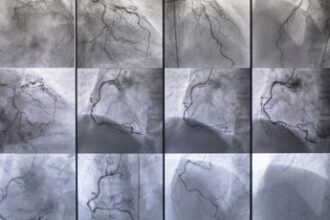

Malattie vascolari responsabili del 22% dei decessi l’anno, al via Consulta

(Adnkronos) - Dietro quasi ogni patologia cronica si trova o si affianca…